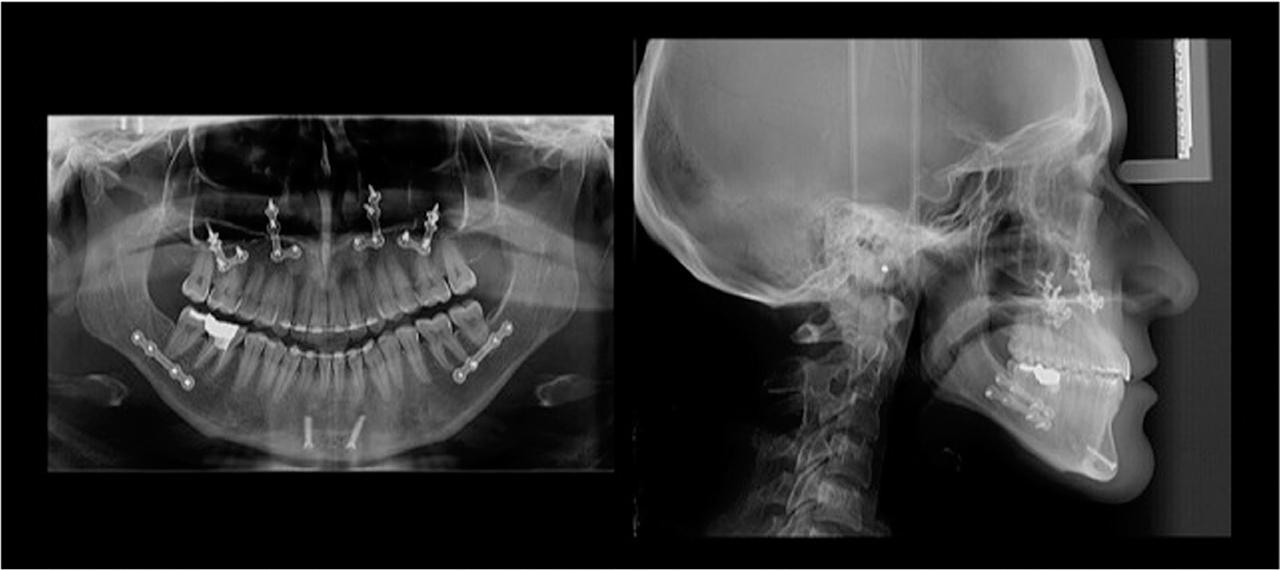

Figure 3

Pre-treatment posteroanterior cephalometric, lateral cephalometric and panoramic radiographs.

Caucasian adult female cephalometric normal values5 revealed a skeletal Class III relationship (ANB = −3.1°, Wits Appraisal = −11.3 mm) highlighted by maxillary retrusion (SNA = 76.9°). The vertical dimension indicated a hyperdivergent growth pattern (FMA = 31.7°) (Table I, Fig. 3). The upper incisor inclination was within the normal range (U1-NA = 24.1°) but the lower incisor inclination was reduced (L1-NB = 19.3°). A postero-anterior cephalometric analysis showed that the maxillary width (JR-JL) was 63.4 mm, and the inter-antegonial notch width (AG-GA) was 86.2 mm, producing a maxillo-mandibular differential of 22.8 mm (Fig. 3). According to the Ricketts/RMO analysis, the maxillo-mandibular transverse differential was 3.2 greater than the Rocky Mountain normal value (the maxillo-mandibular transverse differential index was 3.2).6

Post-treatment photographs in the frontal and lateral views revealed an improvement in facial aesthetics (Fig. 9). The post-treatment cephalometric analysis showed that a skeletal Class I (ANB = 2.1°) relationship was achieved (Fig. 10, Table I). The maxillary and mandibular arches were aligned, the anterior and bilateral posterior cross-bites were corrected and Class I molar and canine relationships were obtained along with an ideal overjet and overbite (Fig. 11). The mandibular midline was corrected with respect to the facial midline and an occlusion with solid intercuspation was achieved (Fig. 9).

Post-treatment panoramic and lateral cephalometric radiographs.

The post-treatment panoramic radiograph showed no significant root resorption (Fig. 10). Upon super-imposition of the pre- and post-treatment cephalometric radiographs (Fig. 12), skeletal and dental improvement was noted. One-year post-treatment photographs and radiographs showed that the treatment results remained stable (Figs. 13 and 14). It was appreciated that the overbite and settling of the occlusion were much better at the one-year review as a result of the resolution of the anterior bite plane effect created by the lingual brackets (Figs. 13, 14 and 15).